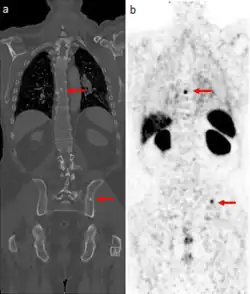

CT scan (left) and gallium PSMA PET scan (right) of patient with prostate cancer metastases in the bones

The positron emitting isotope, 68Ga, can be used to target prostate-specific membrane antigen (PSMA), a protein which is present in prostate cancer cells. The technique has been shown to improve detection of metastatic disease compared to MRI or CT scans.[25]